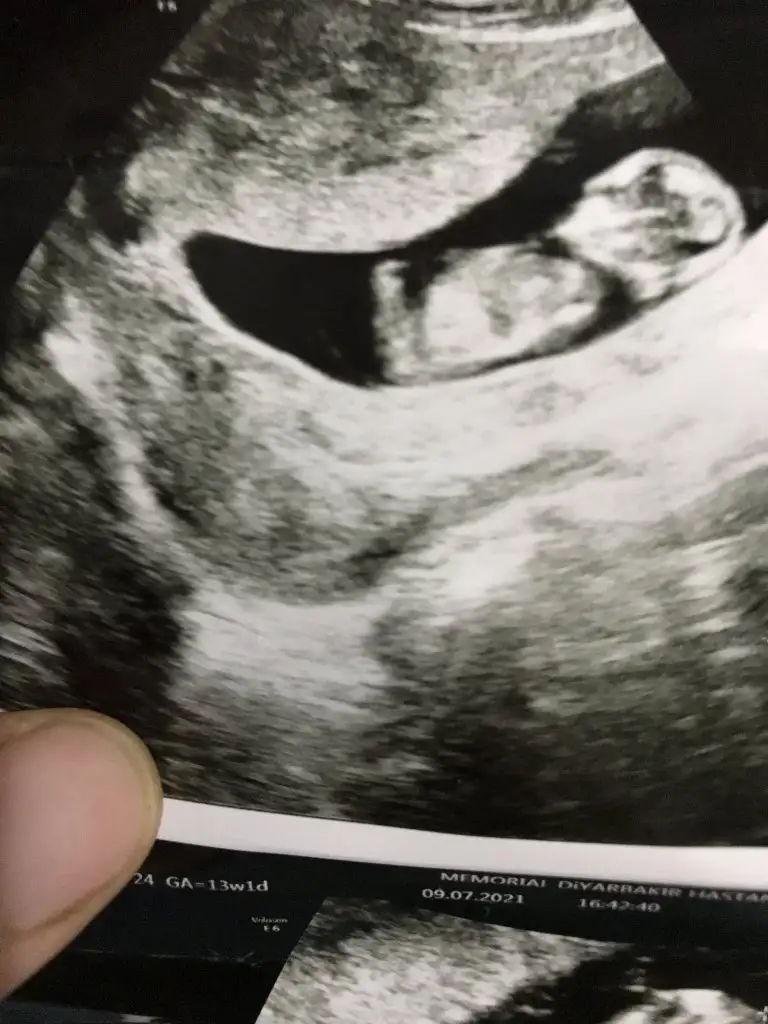

Şimdi arkadaşlar ben 12. Haftada ikili tarama testi yaptırdım sonuçlarında risk düşük çıktı. Sadece free beta hcg Mom değeri düşük çıktığı İçin doktorum sorun olmaz sadece daha sık değerlendirilmen gerekiyor demesine rağmen içim içimi yediği için 14. Haftanın son gün bir daha ikili test yaptırdım. İkinci test sonucu benim için adeta bir şok ve hayal kırıklığı oldu. Başka bir hastanede yaptırdığım ikinci test sonucunda free beta hcg Mom değeri normal çıkmasına rağmen bir anda trisomy 18 değeri 155/1 kadar yüksek riskli çıktı. Ben bunu görünce şok oldum tabi. Doktor keşke ikinciyi yaptırmasaydın kuyuya taş atmış oldun dedi mecburen nifty testi yaptıracağız. Korkular denizinde sürükleniyoruz eşimle beraberşimdi iki test sonucunu da buraya yüklüyorum lütfen bana yardımcı olur musunuz çok korkuyorum.

Öncelikle hamileliğin verdiği hurafelerini aklından çıkar canım yapılan test sadece bir tarama gerçek doğru kessin sonuç değil benim ilk bebeğimde hata edip yaptırdım benim de sonucum kötü gelmiş ve kendimi yedim bitirdim şuan oğlum yanımda uyuyor ve maşallah Aslan gibi bu bebeğimde test yaptırmayacak dedim. Ultrasona girdin mi? Bebeğin ölçümleri nasıl baş popo mesafesi nazal kemik var mı? Ense kalındı kaç çıktı bunlar daha önemliArkadaşlar merhaba lütfen bu konuda herhangi bir bilgisi olan varsa bana yardımcı olsun lütfen eğer okuyorsanız boş geçmeyin ufacık da olsa bir fikriniz varsa belirtin çünkü sabahtan beri çok kötüyüm zor nefes alıyorum.